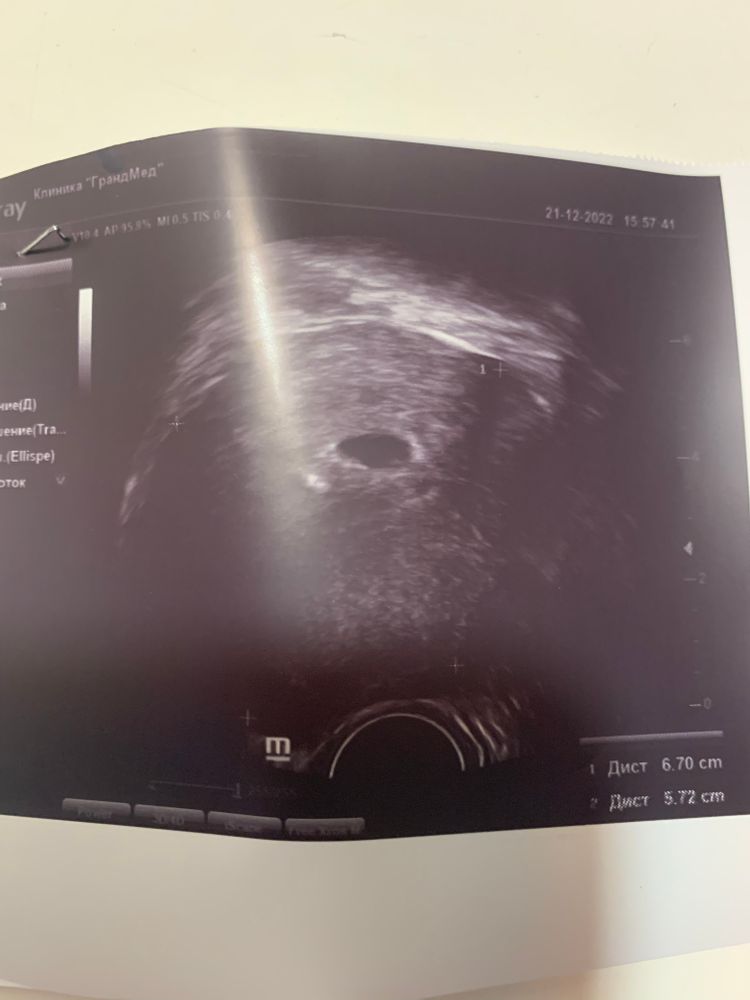

На 21 ДПП должен быть хотя бы желточный мешок

У меня на 19 дпп было УЗИ, мой ре просто подтвердил факт маточной Б, замеры не делал, даже не сказал есть ли ЖМ. Потом сама на фото нашла. А вообще у вас как будто внизу он есть.

На 4-5 неделе уже должен быть жм. Как же нет, когда вот он в правом нижнем углу)) Даже я вижу))

Виктория Кубышкина, как кругляшик такой)) Вот он у вас есть как раз))